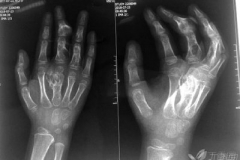

健康科普:如何判斷骨腫瘤?

健康科普:如何判斷骨腫瘤?  一般而言,體表的軟組織腫瘤比較好發(fā)現(xiàn),但是被豐富的肌肉組織等包圍的骨骼病變在早期則不容易被發(fā)現(xiàn),所以專家提倡早發(fā)現(xiàn)、早治療。

健康科普:骨腫瘤是什么?

健康科普:骨腫瘤是什么? 骨腫瘤是一類疾病的總稱,包括原發(fā)的腫瘤和轉(zhuǎn)移來的繼發(fā)性腫瘤兩大類。